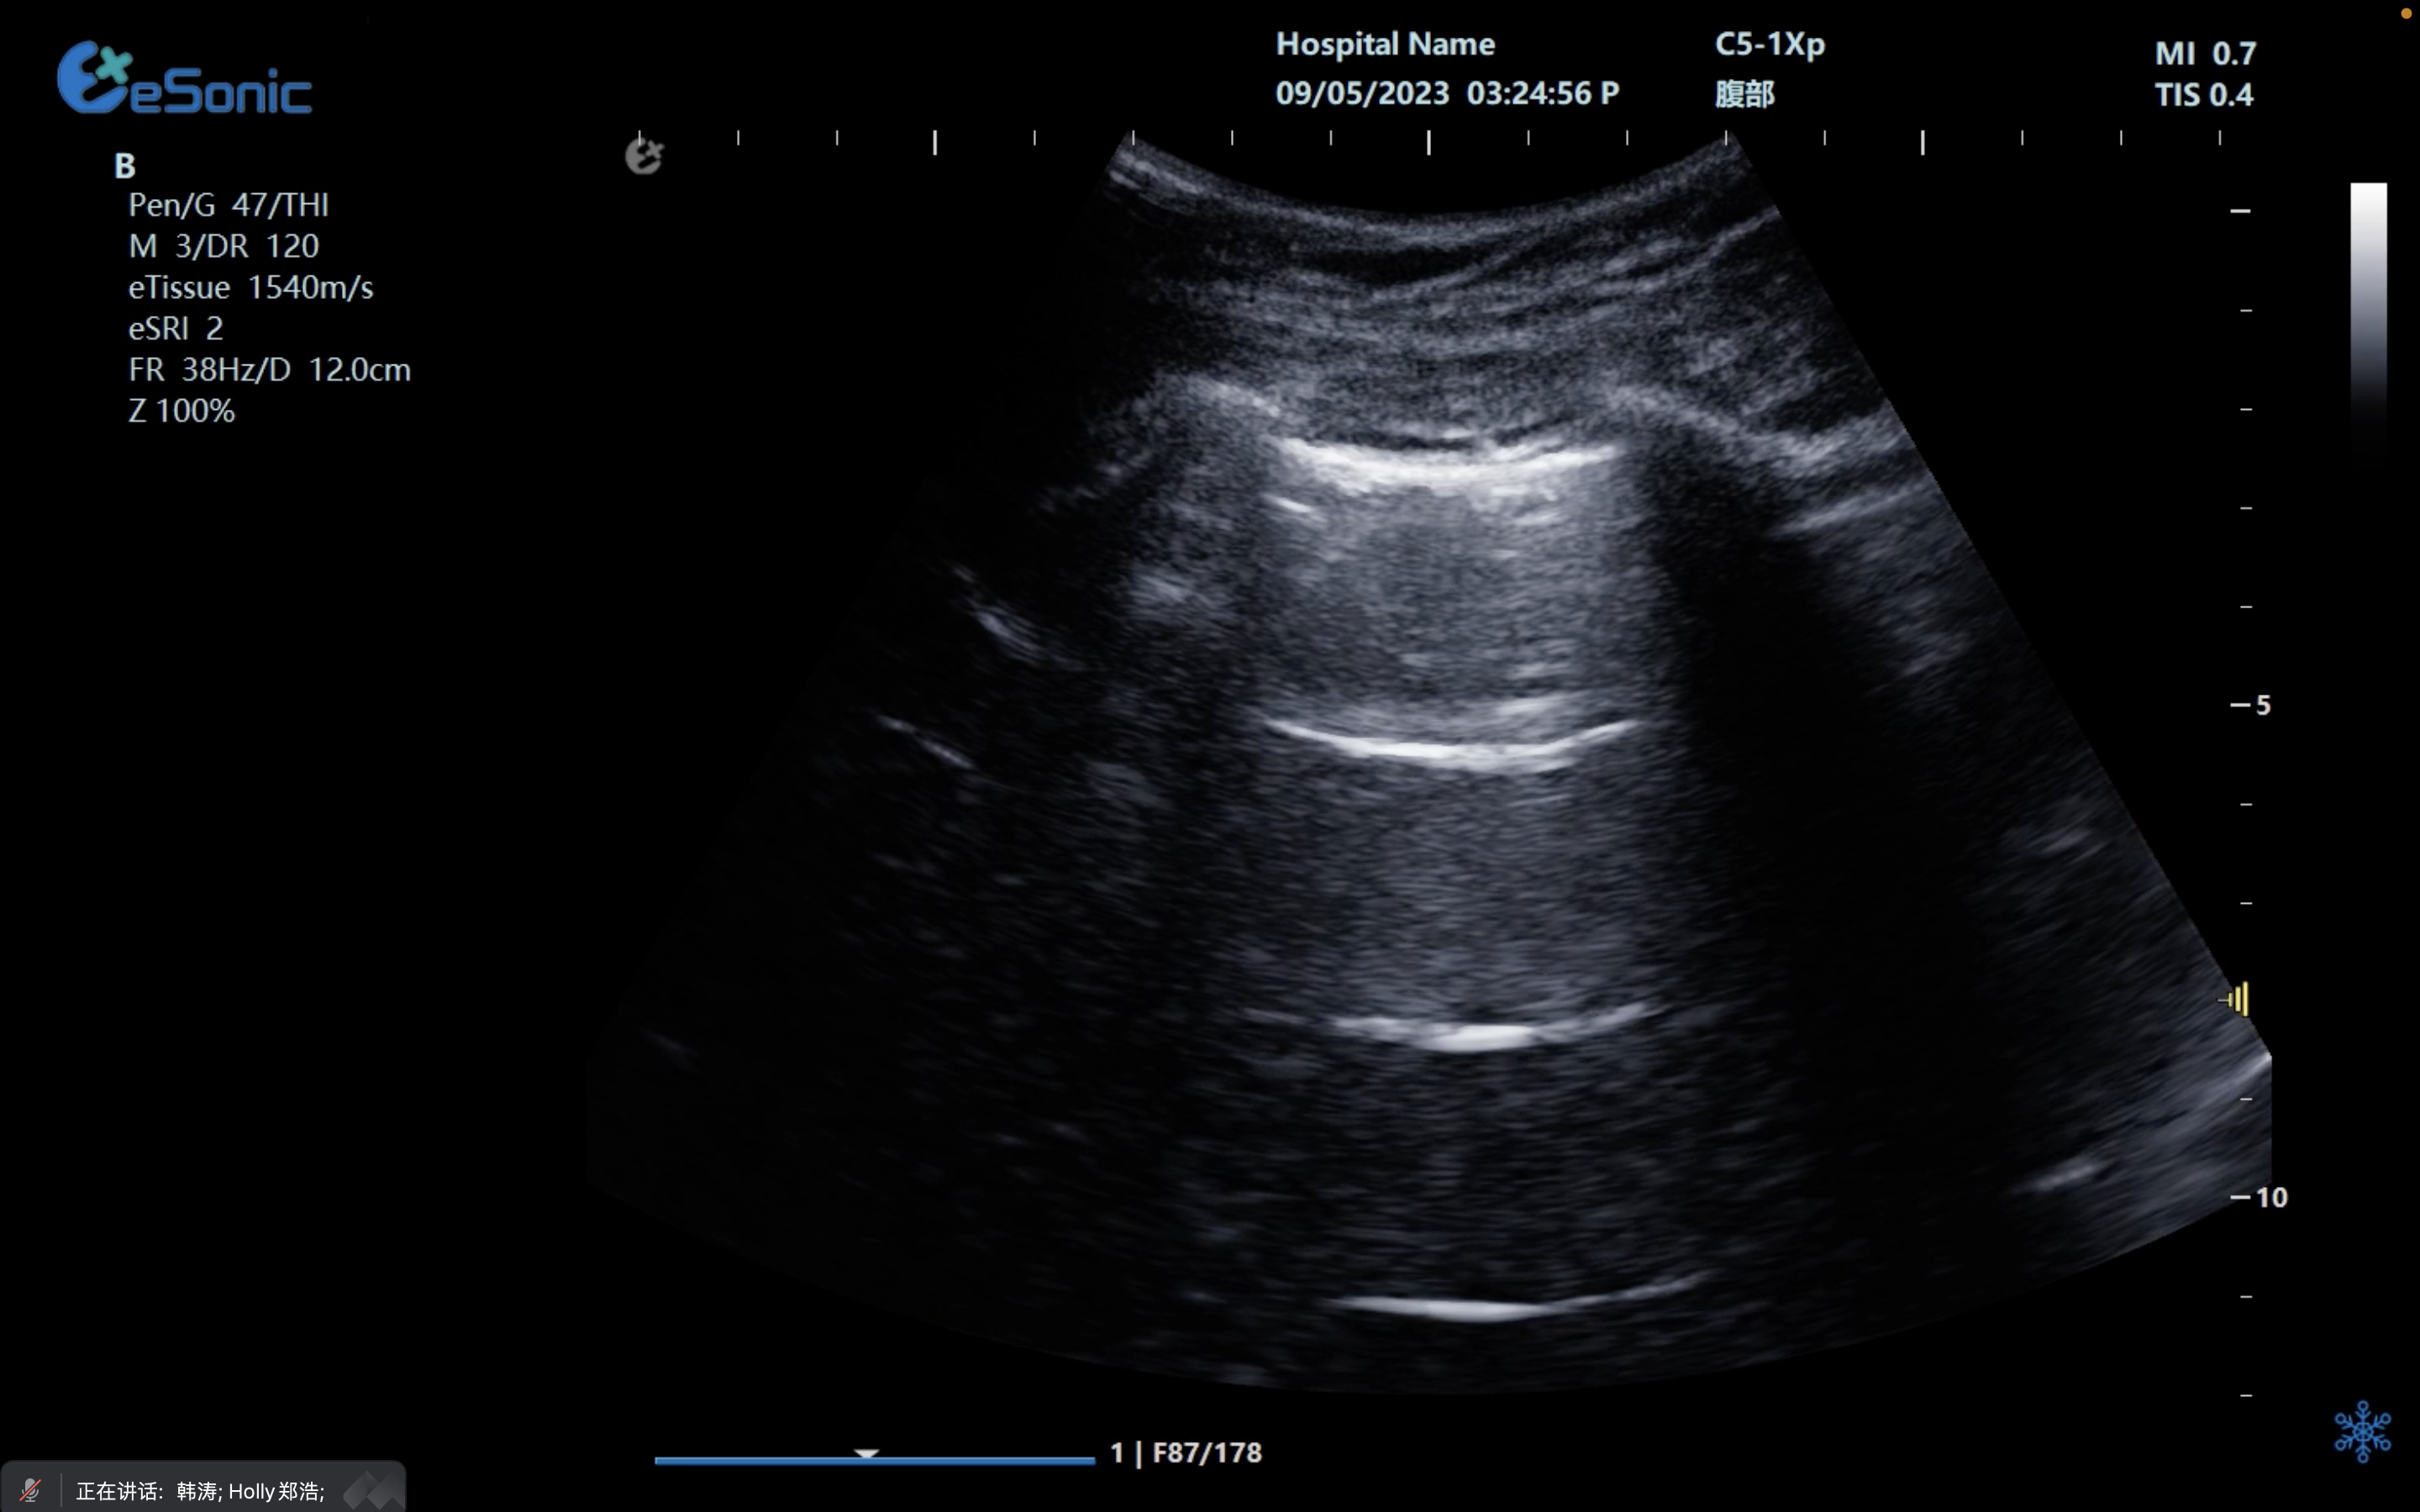

图像清晰?:提供高分辨率、高穿透优异图像,满足急重症卧床病患诊疗,帮助临床医生清晰地看到病灶。急重症.jpg

??图像处理能力?:优质的图像处理功能可以帮助医生更好地分析病情,使医生能够更准确地判断病情。